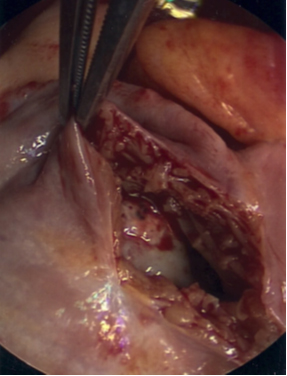

An 81-year-old man with a history significant for hypertension began to experience worsening shortness of breath, fatigue, and lower extremity edema. He was found to have a left upper lobe mass, but a biopsy was non-diagnostic. On further workup, a transthoracic echocardiogram (TTE) showed a large mass within the right atrium, which extended into the right ventricle (Figure 1). The patient had undergone a PET (positron emission tomography) scan, which showed +FDG (fludeoxyglucose) activity within the left upper lobe and mediastinum lymph nodes. The patient underwent a mediastinoscopy and bronchoscopy for tissue but both samples were non-diagnostic. The patient began to show signs of worsening right heart function with increased bilateral edema, elevated jugular venous distention, and complaints of worsening shortness of breath. Cardiac surgery was then consulted for tissue diagnosis and excision of the right atrial mass.